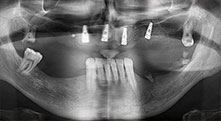

Pr Bratu : Nous utilisons couramment les instruments pour le prélèvement des blocs osseux et le clivage de la crête alvéolaire. Nous utilisons également les scies B6/B7 Piezomed pour l'ostéotomie des dents endommagées et l'extraction des implants défaillants. Bref, toutes les indications qui nécessitent des coupes profondes et propres.

Pr Bratu : Nous préférons prélever l'os sur la crête oblique externe de la mandibule postérieure, et non dans la région interforaminale. Après l'incision des tissus mous, nous utilisons les nouvelles scies pour définir la quantité d'os à prélever. De la même manière, nous les utilisons également pour la totalité de la préparation dans presque 80 % des cas. Nous avons également parfois recours à d'autres instruments piézoélectriques et, pour terminer, à un burin pour mobiliser le bloc. Nous trouvons cette technique chirurgicale très efficace.

Pr Bratu : Nous avons volontiers recours à la technique sandwich pour les augmentations mandibulaires latérales. La préparation d'un couvercle osseux est réalisée à l'aide de la scie piézoélectrique et le fragment crestal est fixé à l'aide de microvis. Nous plaçons un mélange de matériau de substitution osseuse autologue et xénogénique entre les deux. Cela fonctionne très bien. Il faut toujours s'assurer que les coupes verticales aient des dimensions suffisantes lors du clivage de la crête alvéolaire dans la mandibule. Sinon, l'os risque de se casser facilement.